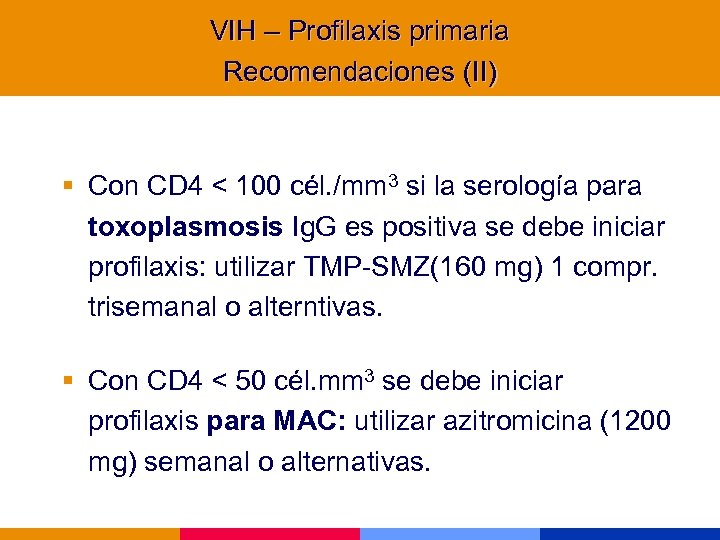

VIH – Profilaxis primaria Recomendaciones (II) § Con CD 4 < 100 cél. /mm 3 si la serología para toxoplasmosis Ig. G es positiva se debe iniciar profilaxis: utilizar TMP-SMZ(160 mg) 1 compr. trisemanal o alterntivas. § Con CD 4 < 50 cél. mm 3 se debe iniciar profilaxis para MAC: utilizar azitromicina (1200 mg) semanal o alternativas.

VIH – Profilaxis primaria Recomendaciones (II) § Con CD 4 < 100 cél. /mm 3 si la serología para toxoplasmosis Ig. G es positiva se debe iniciar profilaxis: utilizar TMP-SMZ(160 mg) 1 compr. trisemanal o alterntivas. § Con CD 4 < 50 cél. mm 3 se debe iniciar profilaxis para MAC: utilizar azitromicina (1200 mg) semanal o alternativas.